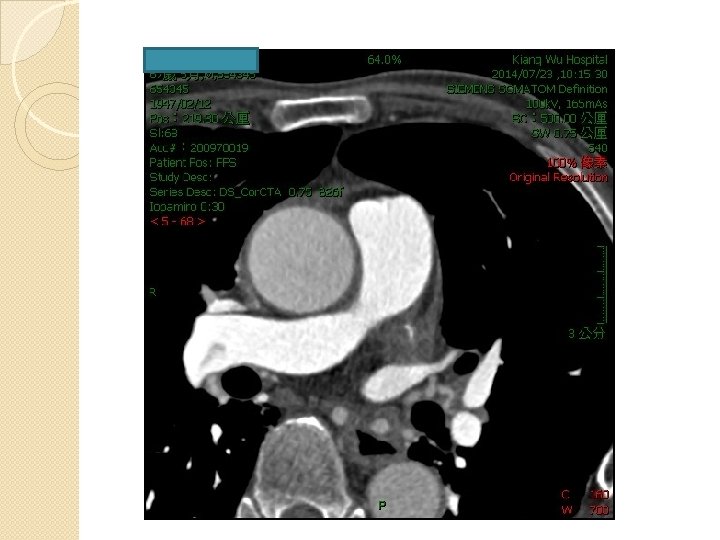

Recurrent drainage of pericardial effusion 400~500 ml drainage Solution /1 st day 10~20 ml drainage at follow time CT (23/7) : No Peri-device Leak , Mild pericardial effusion, No significant contrast extravasation